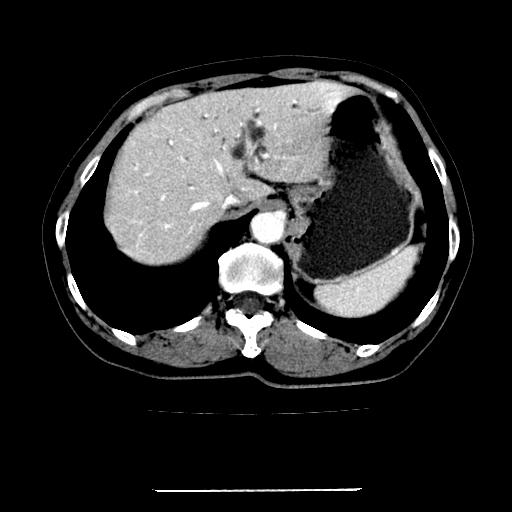

标题: CT22301:女,67岁,上腹部疼痛一周伴皮肤黄染,无发热。 [打印本页]

女,67岁,上腹部疼痛一周伴皮肤黄染,无发热。

左叶肝内胆管结石,并远端肝内胆管扩张。

肝内外胆管结石并肝内胆管扩张。

肝内外胆管结石并肝内胆管扩张

肝内外胆管扩张,左叶胆管内结石

考虑肝胆管癌;胰头占位?【形态失常,体积增大】

1、肝门高密度影下层面和胰头层面可见轻度胆管扩张,而静脉和延迟期均未见扫描完胰头,不能完全排除胰头占位。2、肝门部高密度影,考虑钙化或结石。

考虑肝门胆管癌伴门脉左支受侵包埋,建议mrcp进一步检查。